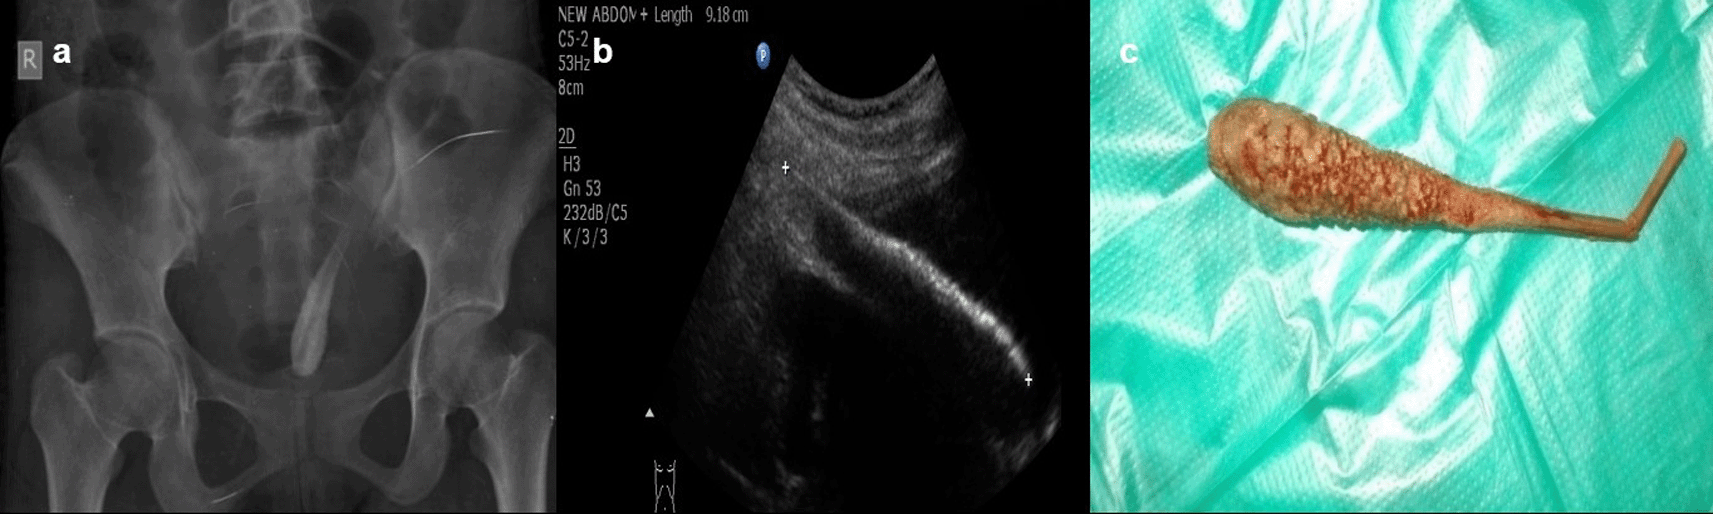

Case 6: A 17-year-old woman came for an ultrasound examination in emergency hours with complaints of severe pain in her lower abdomen. On clinical examination, she had tenderness in the hypogastric region on palpation and no other significant contributing findings. Radiograph Pelvis anteroposterior (AP) view revealed long radio-opacity in the bladder with a radiolucent center that did not look like a calculus, but a foreign body. USG revealed a linear hyperechoic foreign body that penetrated the anterior wall of the bladder. The patient had a history that she had conceived three years ago and had tried abortion by a quack in her village. The patient was operated on and a shaggy piece of a long wooden stick with cotton wrapped around it was found.

The rectum, vagina, urethra, ear, and nose are common places for foreign items to be inserted. These are especially common in children (Figure 5a,b) but can also be seen in adults. The deposition of mineral salts is especially likely to occur in foreign bladder substances, resulting in the formation of bladder calculi (Figure 6a,c). In fact, when a child or young adult develops a bladder calculus, the presence of an embedded foreign body should be suspected.10

USG revealed a linear hyperechoic foreign body that penetrated the anterior wall of the bladder (b). The removed foreign body was a long wooden stick with cotton wrapped around it (c).